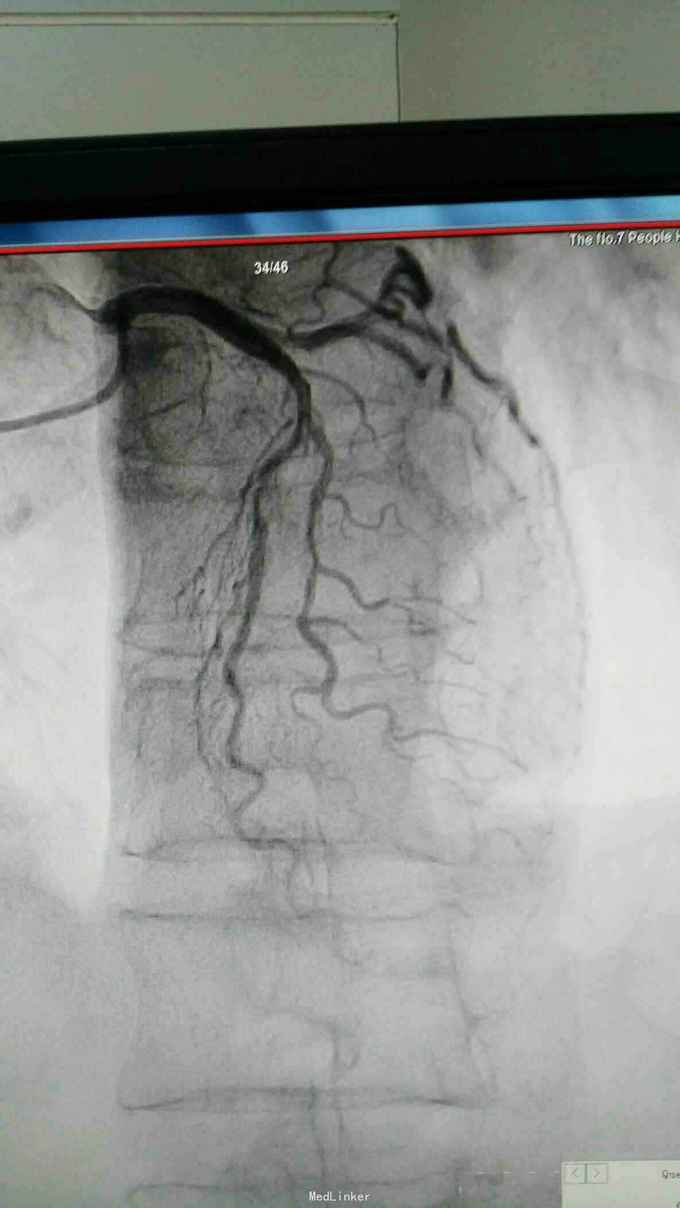

急性下壁心肌梗死,立即启动绿色通道,行急诊冠脉造影明确冠脉病变,必要时PCI治疗,行CAG示:LAD中重度狭窄,LCX尚可,RCA中段局限重度,可见前向血流,选段后降支处重度狭窄,血管钙化明显。考虑此次靶血管为RCA中段处,血管钙化迂曲明显,拟处理RCA,术中导丝到达远端后,预扩球囊反复高压扩张后,支架均无法通过,采用双导丝增加支撑依然无法通过,再更换高压后扩球囊高压扩张,锚定等,最终成功植入支架

急性心梗有时候处理相对较容易,但此病变在于血管钙化迂曲明显,且再次详细阅片后发现局部有“礁石”样病变,预扩球囊及后扩球囊不易扩张,有时需切割或旋磨,但对于急性心梗,如果血流达到理想级别,可不勉强处理,急性心梗中,有些病变为固定狭窄基础上急性血管闭塞,处理并非如一般血栓病变那样容易,造影后仍然需要详细阅片,根据具体病变情况选择合适手术处理方法